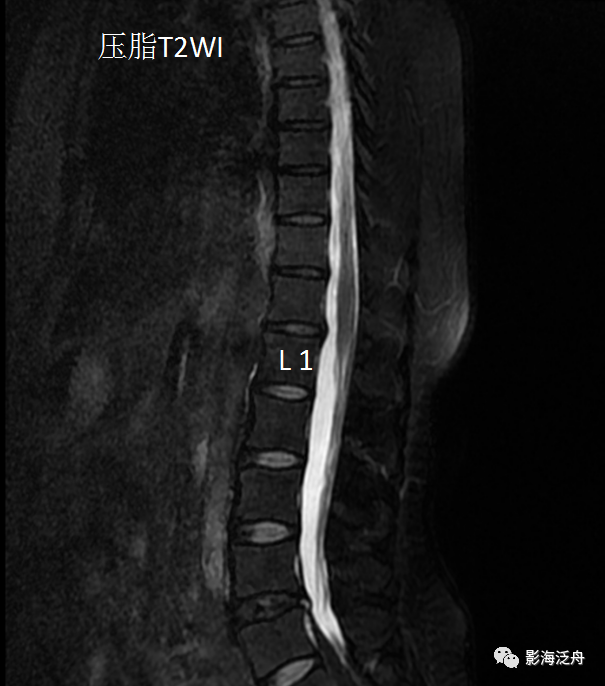

话不多说,上病例:患者女,30岁,因腰骶部疼痛不适1年余就诊,自诉疼痛为间歇性钝痛,可耐受,无下肢疼痛及麻木感,不影响正常生活。患者半年前曾在当地某医院行腰椎MR检查,影像结论为:腰椎轻度退行性改变。此次就诊,临床主诊医生开具了胸腰椎MR平扫检查(可能是想通过扩大检查范围的方法进一步明确病因),影像结论为:所见胸腰椎轻度退变;L4/5椎间盘信号减低伴轻度突出征象。图像如下↓

根据上述影像结论,临床医生推荐患者回家进行保守治疗:平时避免重体力劳动,疼痛症状加重时口服止痛药。患者遵嘱执行1年余,自觉疼痛症状较前加重,于是在上周又过来做了一次腰椎MR平扫检查,图像如下↓